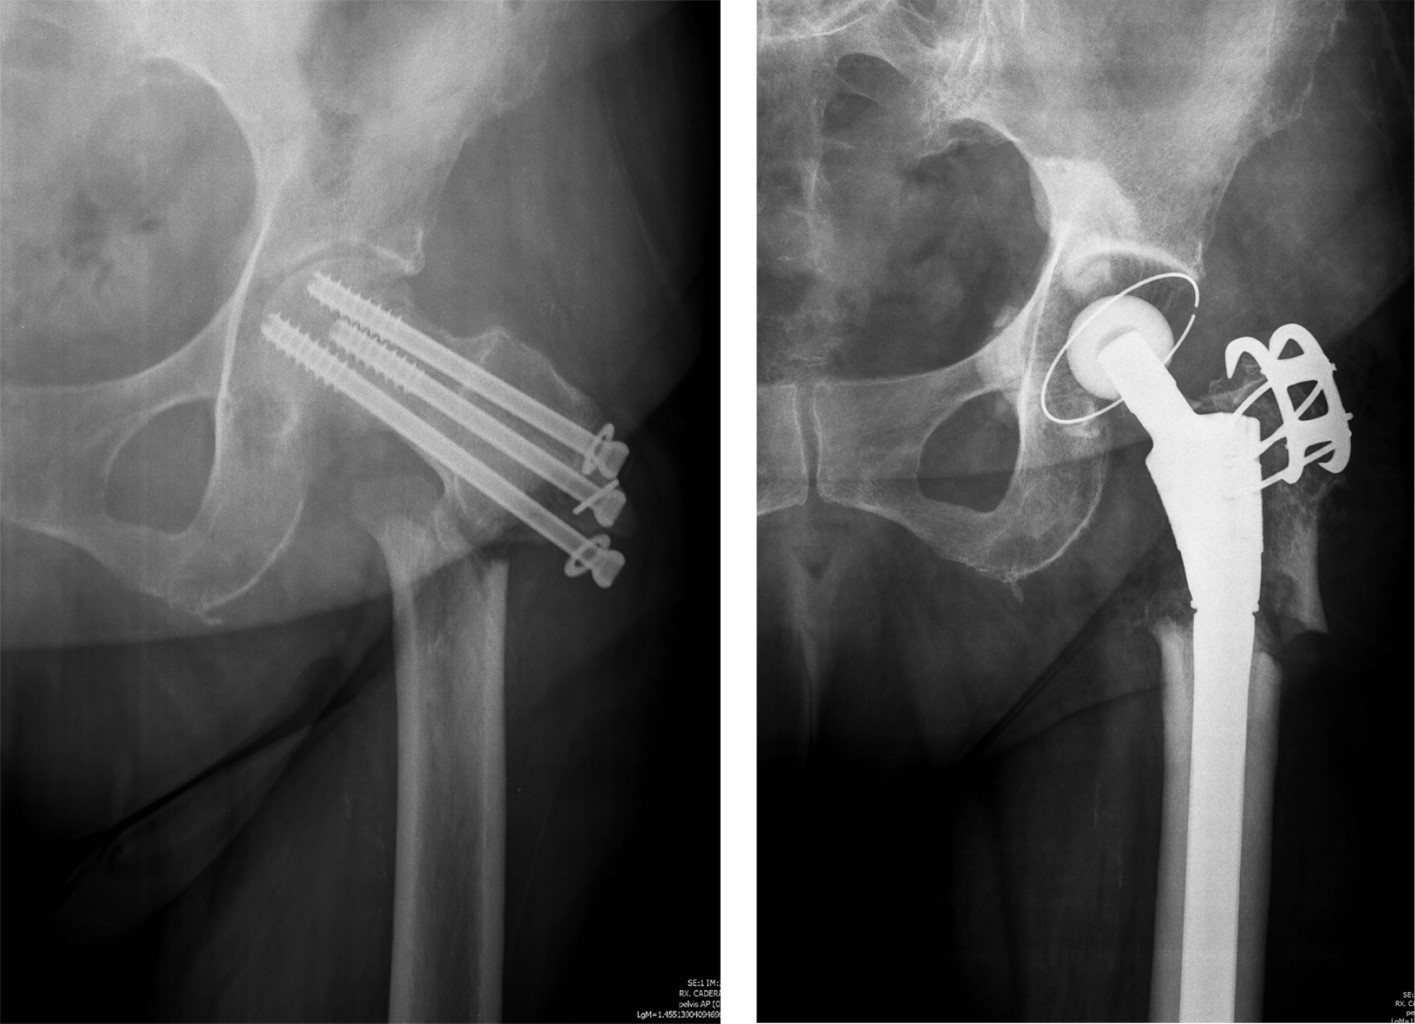

Periosteosynthesis subtrochanteric fractures after fixation of femoral neck fractures with cannulated screws

Introduction: the objective of this study was to analyze the incidence and predisposing factors in subtrochanteric fractures on hips previously treated with cannulated screws after suffering a subcapital fracture, based on eight cases registered in the last 20 years. Material and methods: this is a retrospective observational study on a series of patients with a diagnosis of subtrochanteric hip fracture, who have been treated in recent months for a subcapital fracture of the same hip by osteosynthesis with cannulated screws. The study period was 20 years (2000-2020). Results: of the eight cases, five were women and three were men, with a mean age of 75.12 years (range 59-87 years). In all cases, the subtrochanteric fracture occurred within a year after the first fracture, the time elapsed between the two fractures was four months on average (range 1-9 months). Regarding the disposition of the cannulated screws, most of the 7/8 cases were in the shape of an upper vertex triangle, and only one case was in the shape of an inverted triangle or lower vertex. The entry point into the femoral external cortex was at the level of the lesser trochanter in six cases, and in two cases this entry was distal to the lesser trochanter. Conclusion: in our experience, in the etiology of subtrochanteric fractures, the introduction of screws distal to the lesser trochanter, and the distribution of the screws in a triangular shape are the two main objective predisposing factors.

Figure 7